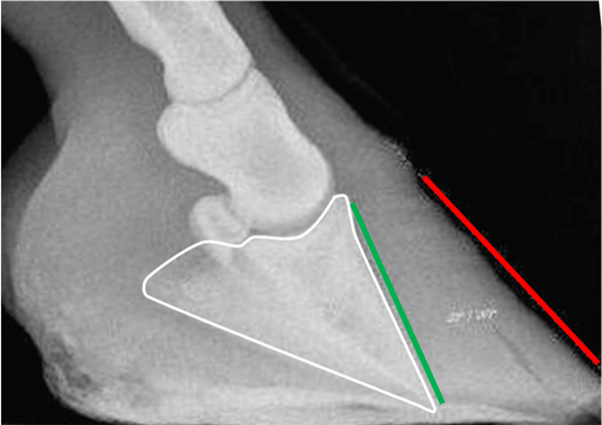

The truth is that: Yes, the hoof has the condition coffin bone rotation, but that is trivial and easy to rehabilitate. Much worse is how close the tip of the coffin bone is to the sole, but that has very little to do with coffin bone rotation and very much to do with incorrect earlier hoof care. In an attempt to make the laminitic toe look shorter, the heel has been left to grow high to rotate the hoof forward, and the toe has been trimmed from underneath to rotate it even more forward. This is serious, very serious, and extremely ignorant, but yes, it can still be rehabilitated, but not by just anyone. I will write a piece that will be called the rehabilitation of traditional trimming.

What does such a hoof look like from the outside? It looks quite low with an almost horizontal coronary band and a long toe. The horizontal coronary band says that the heel is too high and the coffin bone is pointing downwards, the low coronary band has put the coffin bone tip close to the sole, and the long toe is usually laminitic. The natural hoof shape (marked green in the picture below) sticks out below the photographed hoof because someone has trimmed the bottom (thinned the sole) in the front part of the hoof to make the toe look steeper. This is common but very serious, and difficult to rehabilitate.

If the coffin bone was originally parallel to the toe wall, as the white marking suggests, and then “rotated” down to what the radiograph shows, where did all the materia in the red triangle go?

There is never any void inside the hoof where this missing tissue, or the coffin bone, could go. But the missing tissue must have gone somewhere, or?

The answer is that it didn’t go anywhere because the bone has not moved. It was never up by the hoof wall; the hoof wall was down by the coffin bone, and got pressed up by ground pressure after suffering laminitis.

The red line indicates the alleged original angle of the coffin bone.

The green line indicates the current angle of the coffin bone.

The yellow arrow points to pristine sole corium.